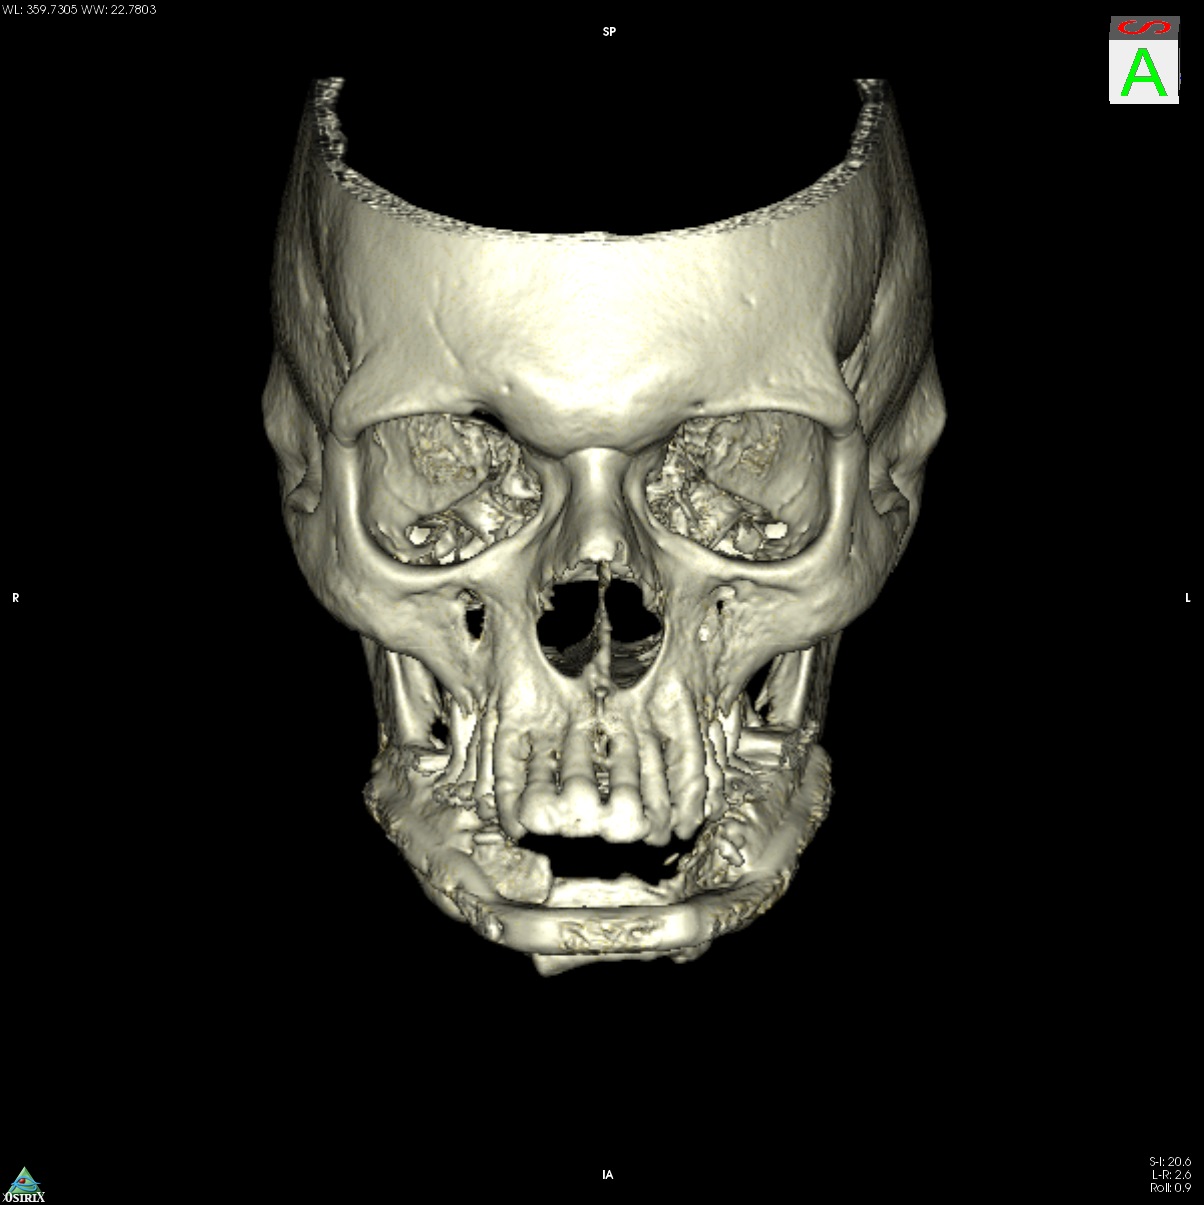

A 58-year old male oncology patient required secondary mandibular reconstruction after composite resection of the floor of the mouth, mandibular symphysis, anterior body regions of the mandible and bilateral limited neck dissection. The existing reconstruction plate bridging the anterolateral mandibular defect was widely exposed through the intraoral mucosa. The chin and lower lip was sagging due to submandibular soft tissue shrinkage and lack of bone suspension. For secondary reconstruction, a two-in-one free flap from the subscapular vascular system containing the lateral scapular border and tip in combination with a latissimus dorsi flap was selected, since severe peripheral arterial occlusive disease prohibited the use of an osteofasciocutaneous fibula free flap. VSP was used to design the bony reconstruction with three sub-segments (total length 8.1 cm) from the right (nondominant arm) lateral scapular border and tip (Fig. 4).

Intraoperatively, the circumflex scapular and thoracodorsal vascular pedicles were dissected to their common subscapular trunk and the angular branch supplying the scapular tip preserved (Fig. 6). In Fig. 6a, the angular vessel branch can be seen emerging from beneath the latissimus island to supply the scapular tip. An elliptical 18 cm x 7 cm myocutaneous latissimus dorsi flap was raised to provide coverage for the extensive submandibular soft tissue deficit. The in toto scapular bone flap was retrieved using the outer frame of the cutting guide (Fig. 6a). In tandem with the vertical rod and its extensions, the wedge osteotomies for segmentation were carried out on a side table (Fig. 6a and c). Prior to the flap transfer into the recipient site, the fit of the neomandibular segments was double checked within the defect of the STL model (Fig. 6d). Microanastomosis was performed end-to-end to the left maxillary artery and end-to-side to the internal jugular vein.

Postoperative imaging confirmed minimal intersegmental gaps to the mandibular remnants with undisturbed healing but limited overall bone volume (Fig. 7a-c). Therefore removal of the PSPMP and a preimplantological augmentation with corticocancellous iliac bone grafts followed 16 months later.